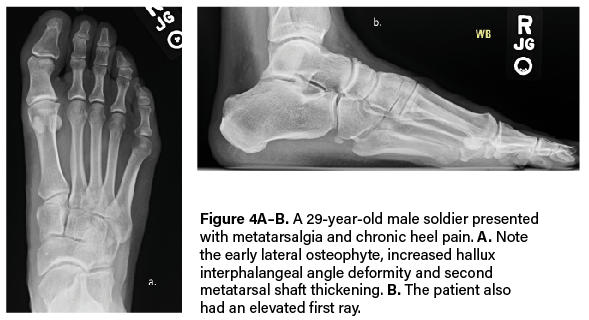

Either way, the multiple classification systems available should not be utilized alone to determine surgical treatment. More often I find that these systems ignore instability, elevation, or metatarsal length. As some studies concluded, classification failed to correlate with every patient.7,8 Roukis and colleagues in 2002 presented his four-stage radiographic analysis—which finally incorporated some radiographic measurements to include metatarsal protrusion, intermetatarsal angle, and talo-first metatarsal angles—which looks at elevatus, as shown in Figure 2 above and Figure 3 below.9 He then followed that up with an article on metatarsus primus elevatus in 2005.10 Then Elliott and colleagues’ 2016 follow-up review11 on Roukis’s 2002 study9 concluded that regardless of the etiology or surgery performed, patients were happier; however, their ROM never improved.

long history of plantar fasciitis. B. The below X-ray shows elevation, with the first metatarsal head not even touching the floor.